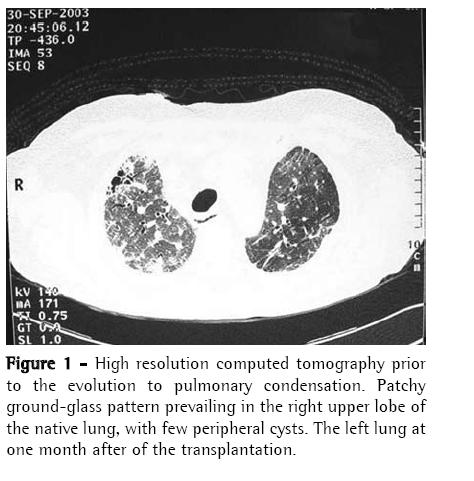

A 56-year-old man diagnosed with IPF (using clinical, functional, tomographic and pathological criteria) five years prior, progressively evolved to dyspnea upon exertion and intense difficult-tocontrol cough with sparse mucoid expectoration. In the month preceding the lung transplantation, he presented hypoxemia and hypercapnia (arterial blood gas analysis with a PaO2 of 57 mmHg and arterial carbon dioxide tension of 45 mmHg at rest on room air at sea level), diffusing capacity of the lung for carbon monoxide at 29% of the predicted value, forced vital capacity of 40.8% (1.41 L), and forced expiratory volume in one second of 52.6% (1.31 L). Pulmonary perfusion scintigraphy revealed arterial flow of 76.7% for the right lung and 23.3% for the left lung. The laboratory tests for collagen-related diseases and the epidemiological investigation of known interstitial diseases were negative. During the five years of outpatient monitoring, the patient had been treated with corticosteroids (prednisone, 0.25 to 1 mg/kg/day), immunosuppressive agents (azathioprine or cyclophosphamide, 0.5 to 2 mg/kg/day), and an antifibrotic/immunomodulatory agent (interferon-γ1b) for four months. The transplantation was unilateral at left, corresponding to the minimal arterial perfusion and the greater intensity of the interstitial involvement according to the high-resolution computed tomography (HRCT) scan. Immediately after surgery, the patient evolved to thoracic instability due to the fracture of three ribs as a result of the osteopenic rib traction during the closure of the incision. He also presented ischemia of severe pulmonary reperfusion (arterial blood gas analysis with a PaO2/fraction of inspired oxygen ratio = 124). The patient was tracheostomized and remained on invasive mechanic ventilation (MV) for ten days, progressively recovering from hypoxemia. The immunosuppressive regimen began with 5 mg/kg of cyclosporine (12/12 h), 0.5 mg/kg/day of prednisone, and 2 mg/kg/day of azathioprine. In addition, anti-basiliximab interleukin-2 antibody was administered on postoperative days 1 and 4. Anti-methylprednisolone antibody (1 g) was also administered postoperatively. The patient was discharged from the intensive care unit to the semi-intensive care unit. However, on the eighth day in the semi-intensive care unit, he presented exacerbation of dyspnea, accompanied by the return of the dry cough and progressive crackling rales throughout the right hemithorax, and was therefore re-admitted to the intensive care unit. The patient was again submitted to an HRCT scan. In addition, fiberoptic bronchoscopy with bronchoalveolar lavage (BAL) was performed, together with transbronchial biopsy of the left lower lobe and the right upper lobe. All cultures tested negative, the BAL fluid presented a neutrophilic pattern, without eosinophils or hemosiderin-laden macrophages, and the histopathological analysis was inconclusive. A pulmonary arteriogram was performed, followed by thoracoscopic lung biopsy in three different regions of the right upper lobe to ensure that the disease was representative (Figures 1 and 2). The pulmonary arteriogram did not demonstrate thromboembolic disease. The biopsy culture was negative for bacteria, fungi, and mycobacteria. Herpes simplex virus and cytomegalovirus tests were also negative. Direct immunofluorescence for Chlamydia pneumoniae, Legionella pneumophila, and Mycoplasma pneumoniae, as well as for antigenuria for L. pneumophila serotype 1, were negative. The histological study of the biopsy of the three right lung areas showed an exclusive pattern of UIP, similar to the left native lung (Figure 3). Pulse therapy with 1 g of methylprednisolone was performed for three consecutive days. The patient remained on invasive MV, then evolved to sepsis caused by infection with Klebsiella pneumophila and Pseudomonas aeruginosa. On day 141 of the hospital stay, after the patient had been on invasive MV and using noradrenaline (0.2 µg/kg/day) for 109 days, transplant of the right native lung was carried out - bilateral sequential transplantation with more than a month interval - regardless of the relative contraindications: high dose of corticosteroid (>20 mg/day), MV, and sepsis treatment. (6)

The radiological imaging demonstrated condensation in the middle, upper, and lower right lobes, and the established diagnosis was IPF exacerbation in the native lung, mainly characterized by the UIP histological aspect (nonuniform and multifocal infiltrate, with inflammatory and fibrous thickening of the alveolar interstitium, pulmonary cysts, peribronchiolar fibrosis, alveolar hyperplasia, and absence of hyaline membranes), and the absence of microbial increase in lung tissues and cardiovascular decompensation. It is known that, in IPF, the lung becomes progressively collapsed, which can simulate images of pulmonary condensation. The accelerated variant of IPF has recently been described and should have its diagnosis characterized by ruling out other causes of exacerbation. The literature mentions, in unilateral lung transplantation, chronic progression of IPF in the native lung. However, there have been no reports of acute progression. This is the first case described in the national literature as IPF in its accelerated phase.